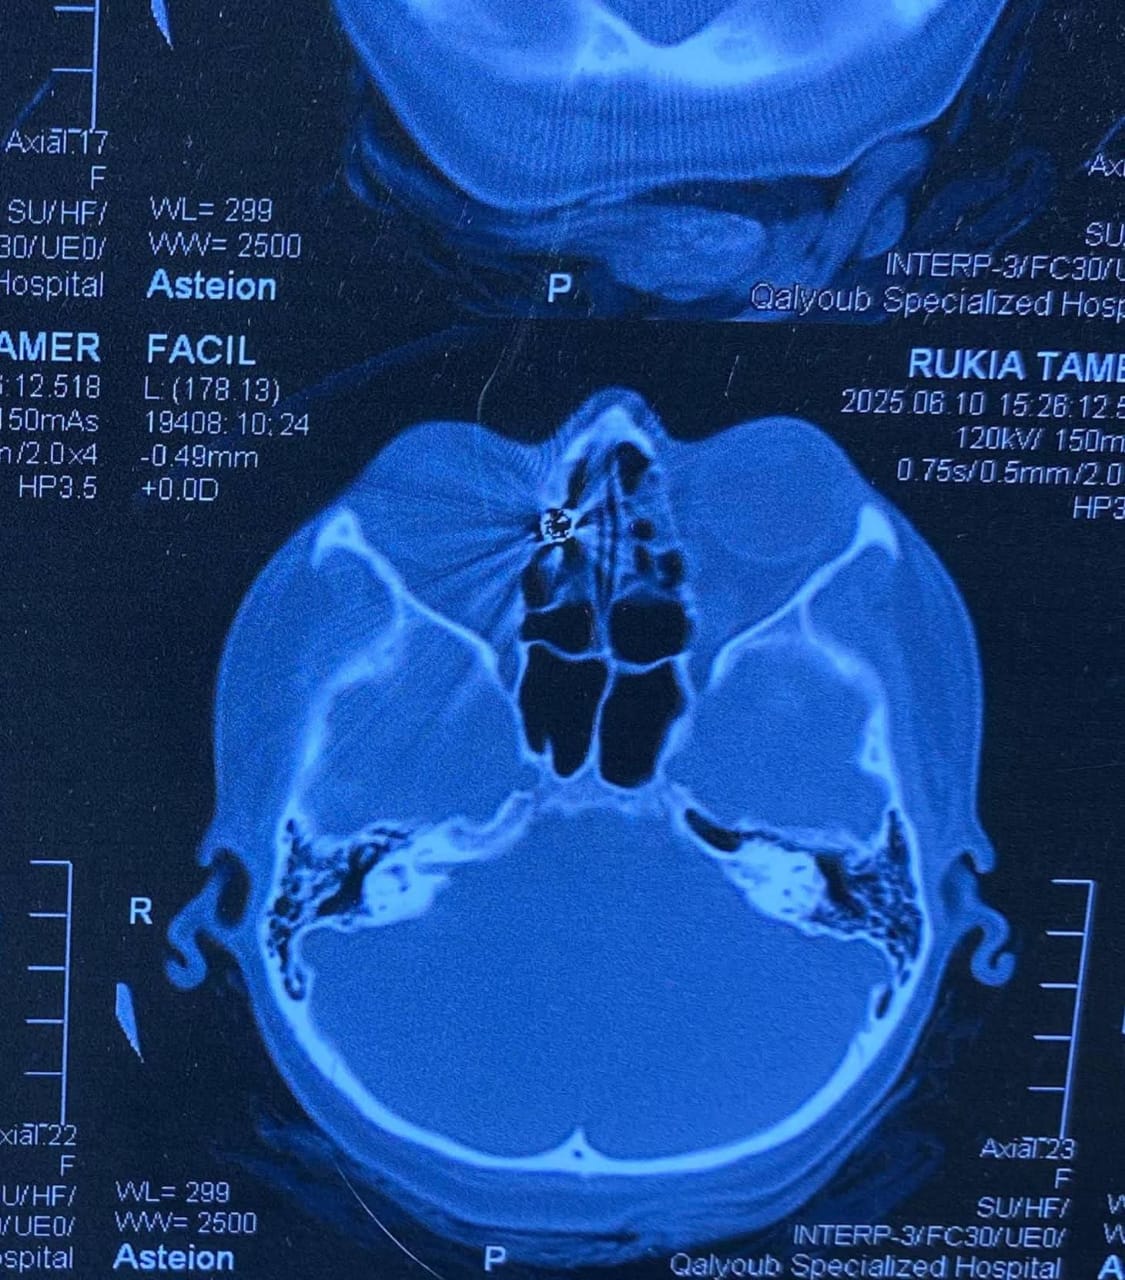

وكانت المريضة قد حضرت إلى المستشفى تعاني من نزيف بالأنف وتورم بالعين، عقب ادعائها الإصابة بطلق ناري من بندقية صيد، وعلى الفور، تم إجراء أشعة مقطعية على الأنف والجيوب الأنفية، والتي أظهرت وجود جسم غريب معدني مستقر داخل الجيوب الأنفية الغربالية.